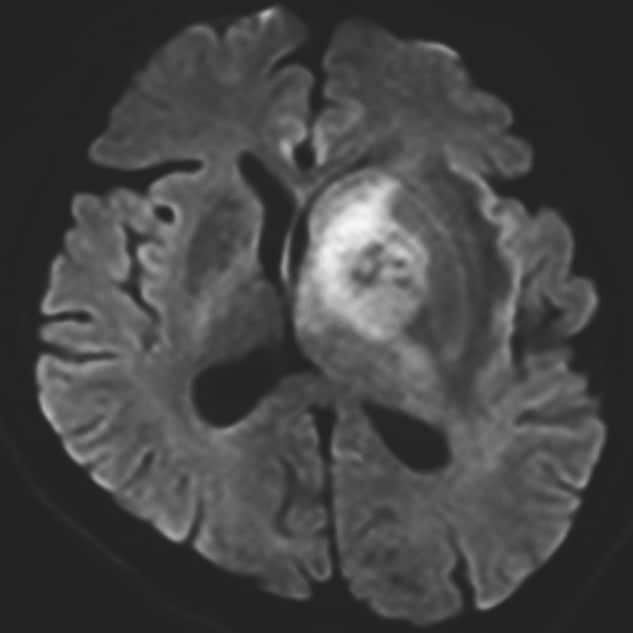

認知機能低下、行動異常、右不全片麻痺の進行を認め、頭蓋内の精査目的に頭部MRIが施行された。左大脳基底核に腫瘍性病変および腫瘍周囲浮腫の所見を認めた。同病変は、造影T1強調像画像では極めて淡い軽度の造影効果を示し、拡散強調画像では軽度の高信号、ADC画像では低信号を示した。診断確定のため生検手術を行った。生検手術1週間後に頭部MRIを施行すると、術前に施行した頭部MRIとは所見が変化し、左大脳基底核の病変は造影T1強調画像では明瞭な造影効果を認め、拡散強調画像でも高信号の増強、ADC画像では低信号を示した。病理組織学的診断は中枢神経系原発悪性リンパ腫であった。そのためR-MPV療法(リツキシマブ、メトトレキサート、プロカルバジン、ビンクリスチン)を施行した。R-MPV療法の経過中の頭部MRIでは、左大脳基底核の病変は縮小傾向を認め、それに伴い初診時に認めていた認知機能低下、行動異常、右不全片麻痺は改善傾向にあり、良好に経過している。